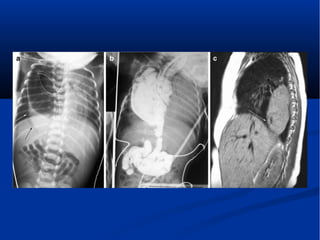

 A 4-day-old infant with a Bochdalek defect and

herniation of solid viscera presenting with mild

respiratory distress. A Chest radiograph shows

bowel in the left hemithorax and a softtissue

retrocardiac mass (arrows). b Coronal

reconstructed, contrast-enhanced CT image

shows intrathoracic herniation of the spleen and

left kidney through a large Bochdalek hernia